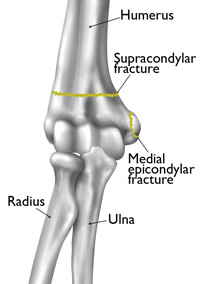

Above the elbow (supracondylar). In this type of fracture, the upper arm bone (humerus) breaks slightly above the elbow. These fractures usually occur in children younger than eight years old. This is the most common type of elbow fracture, and one of the more serious because it can result in nerve damage and impaired circulation.

At the inside of the elbow tip (epicondylar). At the top of each bony knob is a projection called the epicondyle. Fractures at this point usually occur on the inside, or medial, epicondyle in children from 9 to14 years of age.

Common childhood elbow fractures include supracondylar fractures and medial epicondylar fractures.

Reproduced and adapted from J Bernstein, ed: Musculoskeletal Medicine. Rosemont, IL, American Academy of Orthopaedic Surgeons, 2003.